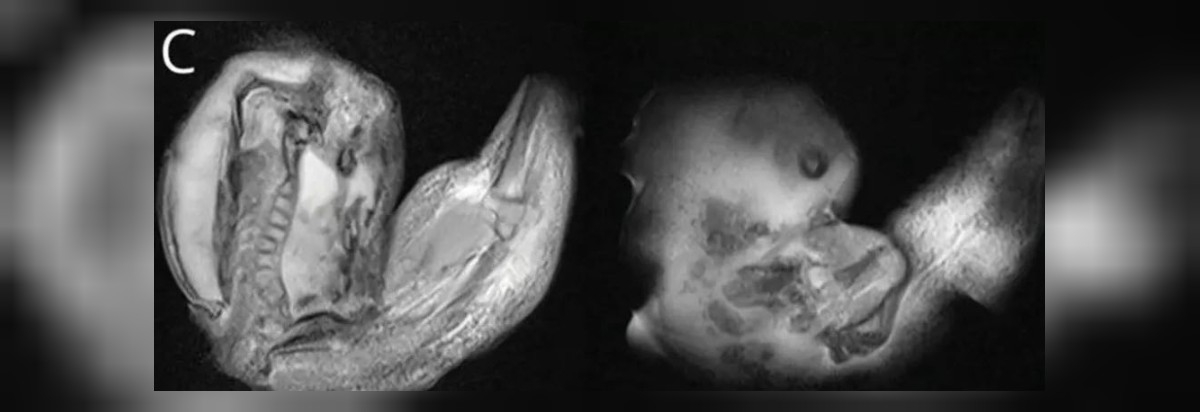

Doktorlar, fetüsün üst vücut kısımlarının, kemiklerinin ve hatta tırnaklarının oluştuğunu, rahimdeki kardeşinin içinde kaldığı süre boyunca büyümeye devam ettiğini belirtti.

TIP TARİHİNDE NADİR BİR OLAY Yaklaşık 10 santimetre uzunluğundaki fetüs, başarılı bir operasyonla çıkarıldı. Bu olay, tıbbi literatürde sadece 18 kere rapor edilen nadir bir durum olarak kayıtlara geçti.